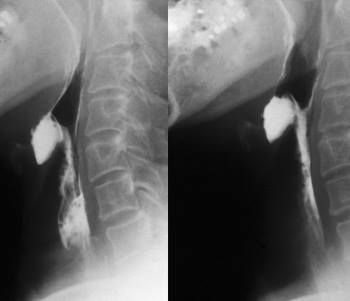

• рентген пищевода и гортани, чтобы определить, насколько глубоко распространилась опухоль;